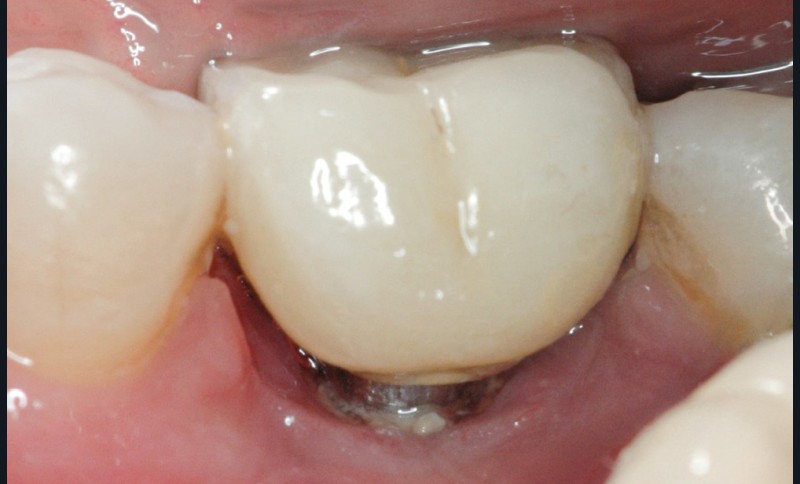

L’implant

- Avulsion de la 36 et régénération osseuse guidée (ROG) réalisée en 2017 suite à une fracture de la dent et une infection

- Un implant posé en 2018 après la fin du traitement orthodontique

- Couronne d’usage scellée, réalisée par son dentiste

- Péri-implantite diagnostiquée en 2021